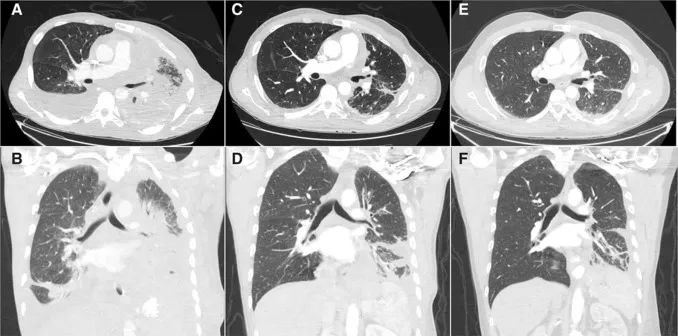

入组的时候,H先生已经发展到了胸壁疼痛、静息时呼吸困难的地步,即使不进行任何活动,也需要长期吸氧。头部CT可见15~20个脑转移病灶,没有症状。

他作为一名NTRK融合突变的受试者,参加了恩曲替尼的临床试验。开始治疗仅仅3周,H先生的疼痛与呼吸困难症状就明显消退,摆脱了呼吸机!

26天时复查的CT扫描显示,H先生的病灶足足缩小了47%;胸腔积液消退了,肺萎缩症状也有了缓解,各种症状体征都在向着好的方向发展;至155天复查的时候,H先生高兴地发现自己的癌症还在消退,与入组接受治疗之前相比,足足缩小了77%!

此外,入组之前就存在的那接近20个脑转移病灶,也全部消失了!